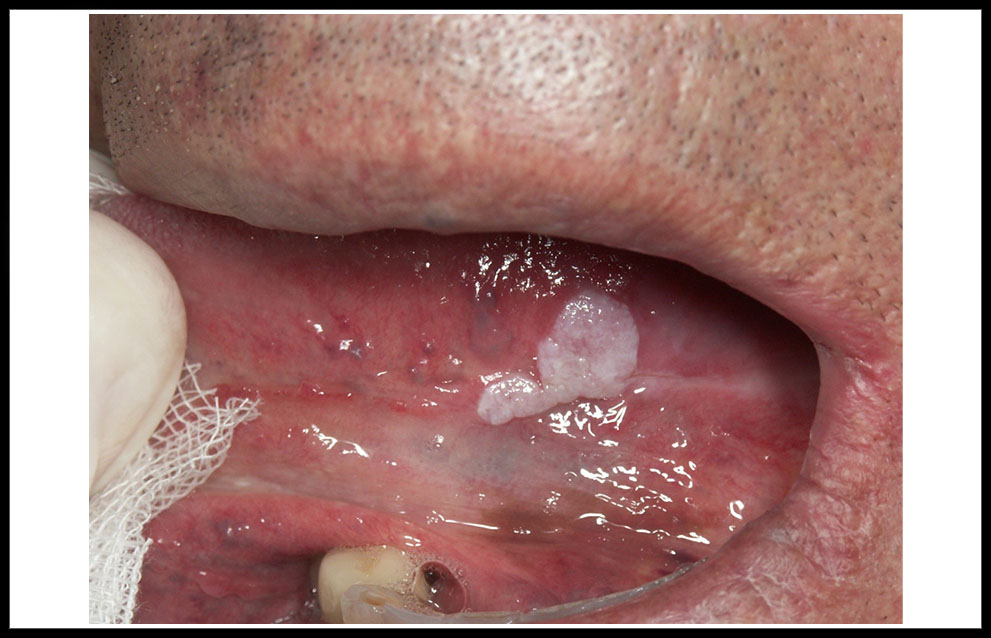

La leucoplasia oral aparecen con una frecuencia algo superior en hombres (6/4), en edades comprendidas entre los 40 y 60 años. Desde el punto de vista clínico, una clasificación clásica considera 4 tipos esenciales der leucoplasia que tienen una correspondencia pronóstica. Las formas homogéneas son placas homogéneamente blancas que pueden presentar pliegues más o menos profundos (figura 1). Las leucoplasias no homogéneas integran a su vez tres subtipos: Las denominadas leucoplasia nodulares retrocomisurales, frecuentemente infectadas por Candida albicans (figura 2); las eritrolecucoplasias, que asocian áreas blancas y rojas (figura 3); y las leucoplasia verrugosas, que presentan una superficie verrugosa con aspecto parecido al de una coliflor (figura 4). Un tipo clínico especial, no incluido en la clasificación precedente, está constituido por la leucoplasia verrugosa proliferativa. Se trata de una lesión blanca que aparece en mujeres de edad avanzada, no fumadoras ni bebedoras, inicialmente limitada, aunque progresivamente expansiva afectando a zonas amplias de la mucosa oral, especialmente la encía y el paladar, y asociada a un riesgo muy elevado de desarrollo tumoral múltiple de cavidad oral (figura 5).

Figura 2. leucoplasia nodular retrocomisural